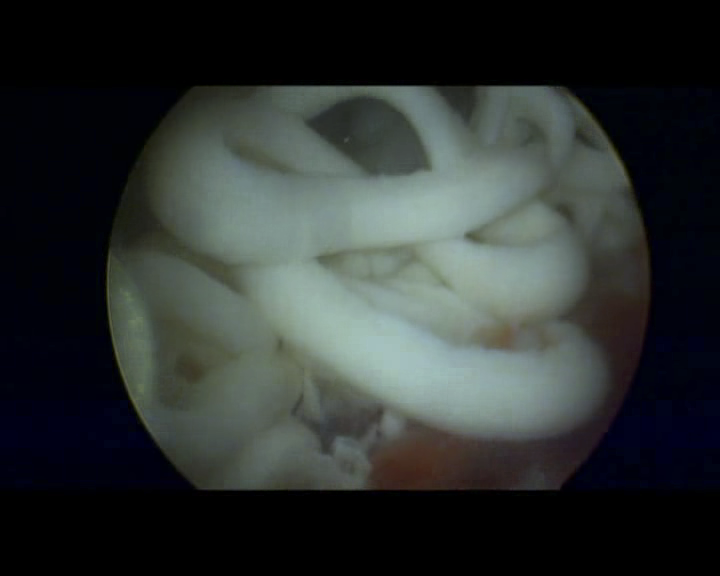

• 我院男科首例显微镜输精管附睾吻合术宣告成功

我院男科首例显微镜输精管附睾吻合术宣告成功

术后经过两个半月的康复,我院男科收到2016年9月18日手术治疗梗阻性无精子症患者传来的喜讯:在当地医院检查精液显示找到精子,标志着我院男...

• 精液射,“小蝌蚪”飞——我院男科首例显微镜输精管附睾吻合术宣告成功

术后经过两个半月的康复,我院男性科收到2016年9月18日手术治疗梗阻性无精子症患者传来的喜讯:在当地医院检查精液显示找到精子,标志着我院...